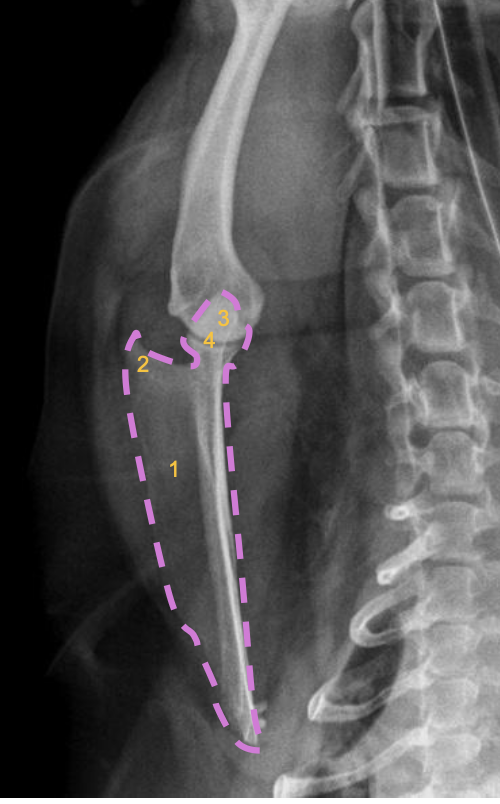

what radiographic view of the humerus is shown?

cranio-caudal view